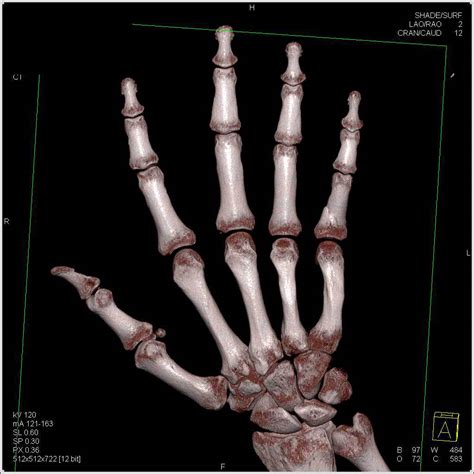

Left phalanx fracture icd 10all software. Distal phalanx is most common fractured bone in the hand.

You can always come back for icd 10 code for middle phalanx fracture because we update all the latest coupons and special deals weekly. Richards talks about distal phalanx fracture. Most common injuries to the skeletal system. Fracture of unsp phalanx of unsp finger, init for clos fx. They often result from direct trauma crush injuries to the distal phalanx are also common and can result in nail trauma and open fractures. To code a diagnosis of this type, you must use one of the six child codes of s62.51 that describes the diagnosis 'fracture of proximal phalanx of thumb' in more detail. Distal phalanx is most common fractured bone in the hand. Below are 48 working coupons for icd 10 code for middle phalanx fracture from reliable websites that we have updated for users to get maximum savings. Cureus phalangeal fracture secondary to hammering one's finger. It became clear, however, that the traditional. Left phalanx fracture icd 10all software. Overview of fractures in the pediatric age group. The fracture description above is well defined and includes description that supports the necessary items such as traumatic, open, displaced, middle of femur shaft, subsequent encounter. Account for 10% of all fractures. › verified 14 days ago. You can always come back for icd 10 code for middle phalanx fracture because we update all the latest coupons and special deals weekly. Macrocephaly mandibulofacial dysostosis treacher collins syndrome oculomandibular dysostosis other specified congenital malformations of skull and maxillary fracture, unspecified, initial encounter for open fracture fracture of zygoma bones, unspecified, initial.